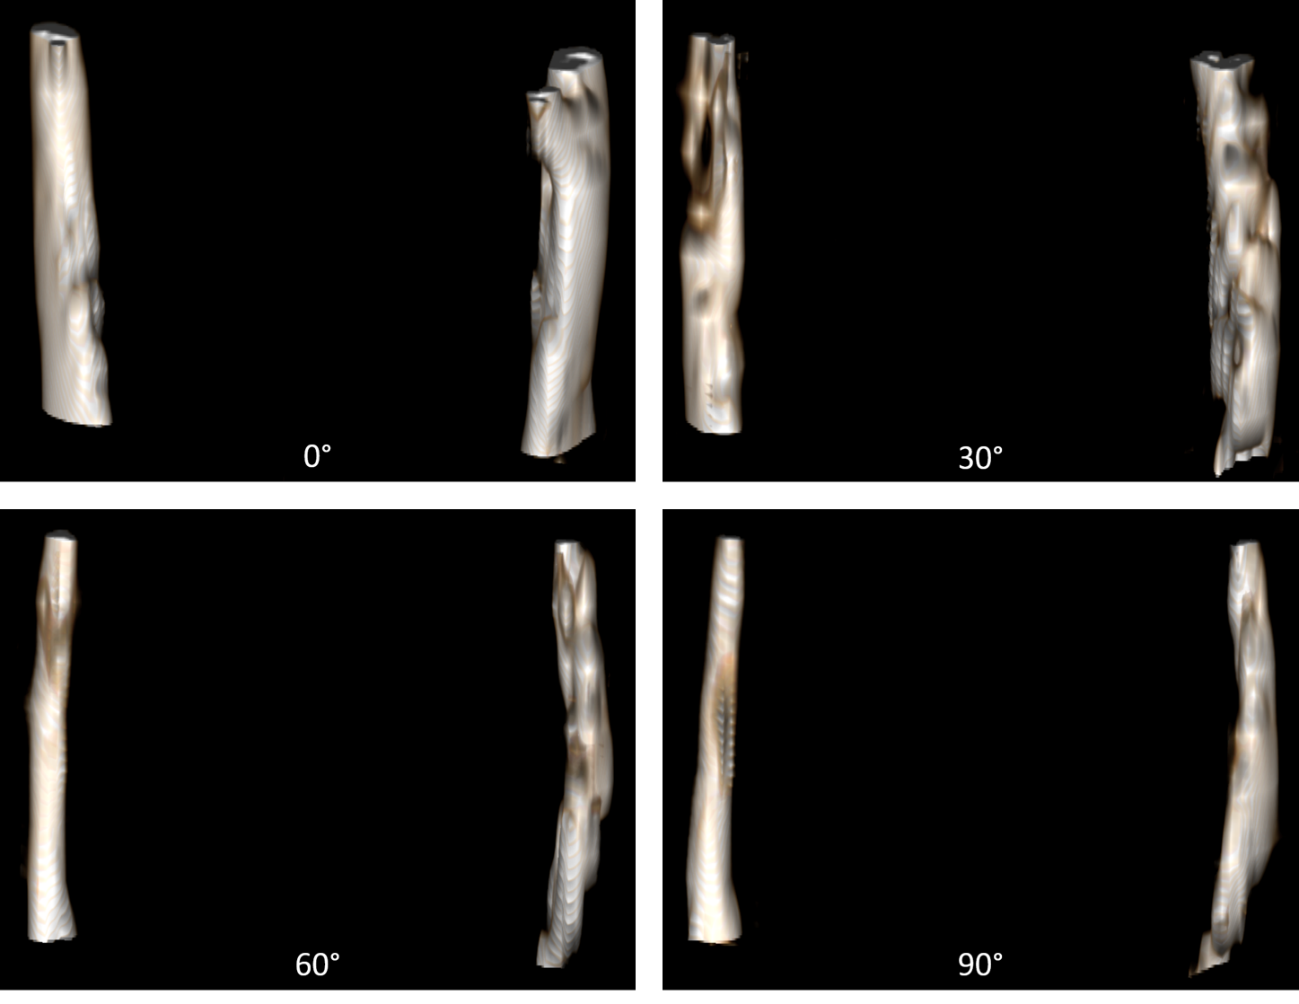

Figure 2 3Dsegmentations Of The Internal Jugular Veins At 0 supine

https://cds.ismrm.org/protected/19MProceedings/PDFfiles/images/1020/ISMRM2019-001020_Fig2.png